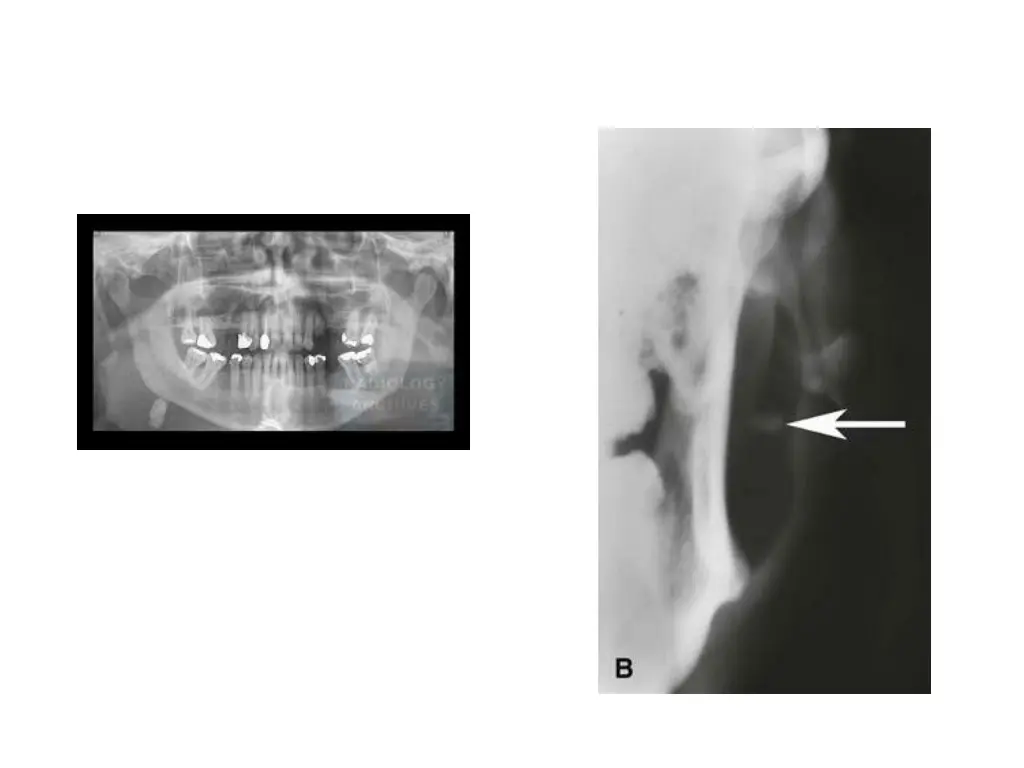

Effects of internal radiation therapy Disseminated thyroid cancer is treated by removal of thyroid gland To insure all thyroid tissue is removed or destroyed, pts are given radioactive iodine (131I) after surgery R active iodine is taken up not only by thyroid tissue but also by oncocytes in salivary gland tissue R active iodine can cause permanent salivary gland damage and fibrosis resulting in salivary gland hypofunction

Clinical presentation Pts with DTC treated with radioactive iodine may experience xerostomia and decreased salivary gland function Treatment: following administration of r active iodine, pts should suck o lemon drops or chew gum to stimulate salivary flow This will aid in clearing radioactive iodine from salivary glands and potentially decrease gland damage